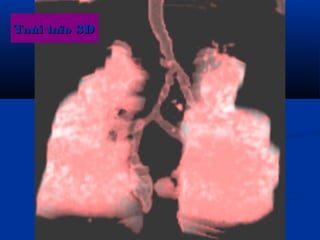

Taùi taïo 3DTaùi taïo 3D

U maùu vuønghaømU maùu vuøng haøm (T)/(T)/ Daõn tónh maïchDaõn tónh maïch caûnh ngoaøi (T)caûnh ngoaøi (T)